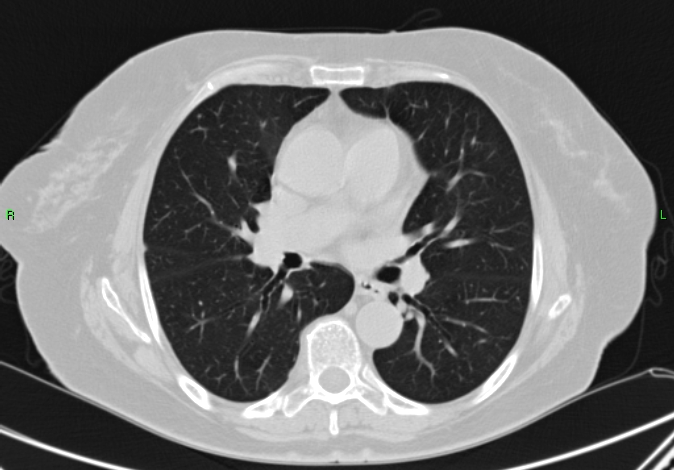

3b: Multiple lung metastasis, CT lung window (axial, coronal reformat)

3c, coronal reformat

70 year old man, colon tumor.

CT: Numerous 1-6 cm round and irregular, lobulated-spiculated contrast enhancing lesions in both lungs, everywhere sporadically.